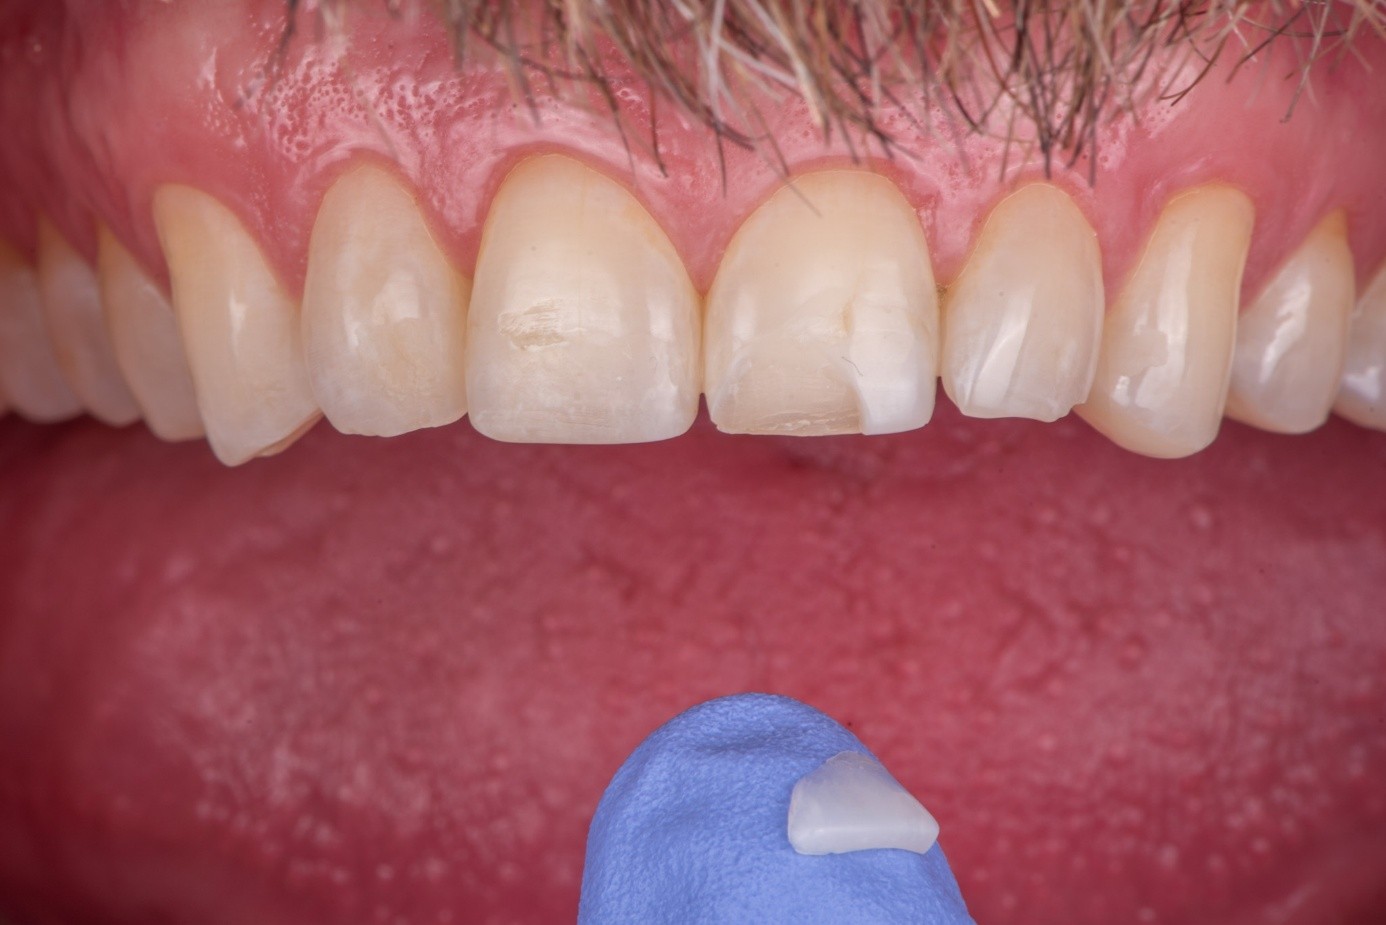

Case 1: Broken Feldspathic Veneer

This case involved a patient with multiple feldspathic porcelain restorations done more than 15 years ago in the esthetic zone. Multiple restorations presented with tissue recession and marginal discoloration, some also presented with microcracks that were visible during clinical examination and were in need of replacement in the near future. However, the patient was not financially committed to replace the other failing restorations. Maxillary right lateral incisor presented with an unusual failure pattern: The incisal third remained fully bonded and intact, while the middle-to-cervical portion of the veneer was fractured away as a single piece (Figure 2). This type of fracture could be described as a cervical shear fracture with incisal retention—a form of mixed failure, since part of the restoration remained bonded but the majority separated cleanly. Examination revealed almost no adhesive layer on the tooth surface, while the fractured restoration still showed adhesive remnants (Figure 3). This indicated that the weak point was the interface between adhesive and tooth substrate, rather than between ceramic and adhesive.

The likely etiology was multifactorial: a pre-existing microcrack from the fabrication process, flexure of the tooth under function (particularly during protrusive movements), or minor trauma to the cervical third. Because the fragment was intact and fitted precisely, a decision was made to re-bond the fractured piece rather than replace the entire restoration.

(2.) An intraoral view of the maxillary anterior region, where most teeth are restored with ceramic facings. The upper lateral incisor is fractured, with only the ceramic in the incisal third remaining in place. The cervical and middle thirds of the facing are lost, exposing the underlying tooth structure.

Figure 2